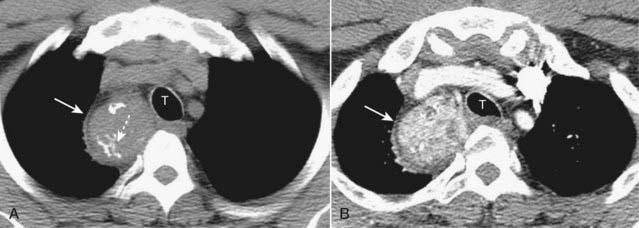

image

Figure 12-24 Infected bulla.

A, Several thin-walled, but air-containing, bullae are shown in the right upper lobe (solid white arrow). B, Several weeks later, one of the bullae (dotted white arrow) contains both fluid and air (solid black arrow). Bullae normally contain air but can become partially or completely fluid-filled from infection or hemorrhage.

Figure 12-25 Bullous disease.

Bullae measure more than 1 cm in size. They have a very thin wall that is often only partially visible on conventional radiography. CT demonstrates them more easily (solid white arrows). Characteristically, they contain no blood vessels but septae may appear to traverse the bulla. On conventional radiographs their presence is often inferred by a localized paucity of lung markings (see Fig. 12-24A).